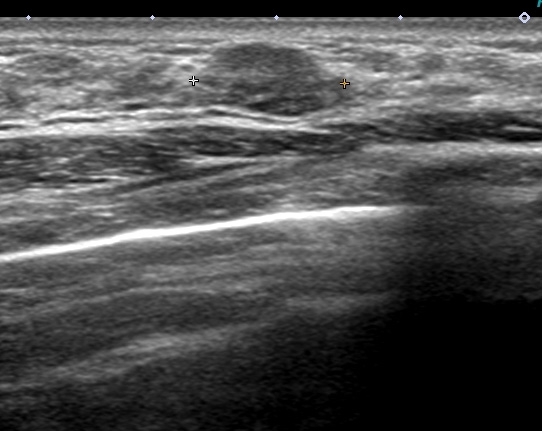

これも検診時の画像

左はエラストグラフィー(硬さを見ています 赤:柔らかい 青:硬い)

皮下脂肪は赤で柔らかく

腫瘍(中心:青)は周囲の乳腺(緑)よりも硬いことがわかります。